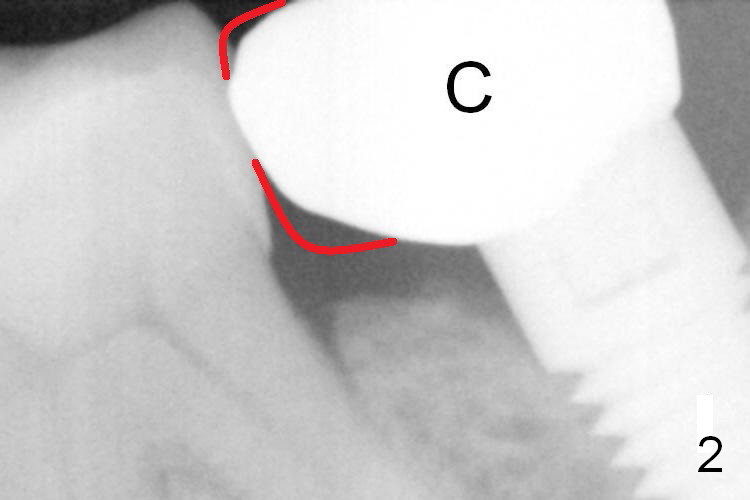

A 65-year-old woman was pleased with functionality of the implant crown at #18 immediately post cementation (Fig.1 (taken 6 months post cementation).  In 2 years and 8 months, she complains of gingival irritation after food impaction.  Although the proximal contact is slightly light with floss, the gingival embrasure feels to be extremely large (Fig.1 *).  When the crown is to be remade, increase the vertical contact (Fig.2 red line) to close the gingival embrasure as much as possible.  PA taken immediately before redo shows that there is no gap between #18 and 19 (Fig.3).  When the crown is being cut off, the gingiva is tender.  It appears that the existing crown (made by Classic Craft) has overextended margin.  When the new crown is being fabricated, trim the margin of the die very well.   The margin of the new crown should be shorter (Fig.3 red curved line).

Clinically the existing crown is a little too small (Fig.4).  Since the implant is not too small (5 mm in diameter) and has been placed 3 years 4 months, the implant must be well osteointegrated (take PA and BW).  The crown should be as wide as possible buccolingually with the wide buccolingual contact.